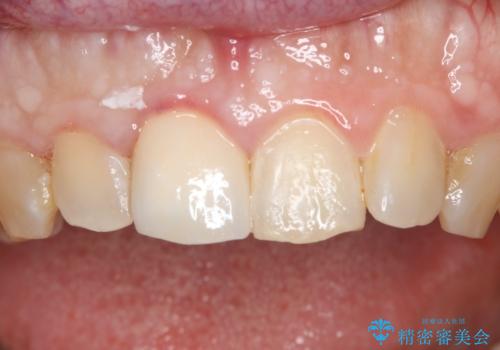

前歯が綺麗になったと大変満足して頂けました。